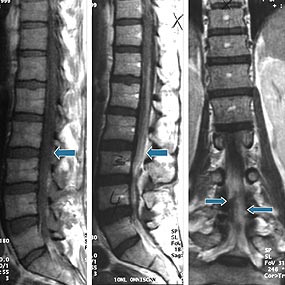

Et annet meget alvorlig problem illustreres av sykehistorien til pasienten 5, som utviklet epiduralabscess. Pasienten fikk flere akutte, kliniske symptomer og tegn på epiduralabscess (dag 43) i form av nevrologiske utfall med blæreparese, økende smerter i korsryggen samt høy feber, stigende CRP- og LPK-verdier. Det tok allikevel 15 dager fra mistanke om en epidural prosess ble fattet til pasienten ble operert. Dette er veldig lang tid når vi vet at en rask diagnose og kirurgisk dekompresjon er kritisk både av hensyn til overlevelse og alvorlig nevrologisk sekvele (8, 22). Det ble tatt tre serier med MR-bilder av columna med og uten kontrast som ble tolket som negative med henblikk på en ekspansiv prosess (fig 1). Gransker man litteratur vedrørende utseende av abscess på MR, viser det seg at noen fremstår som en ekspansiv prosess med kontrast oppladning svarende til granulasjonsvev. Andre derimot fremstår som diffus prosess som kan involvere mange spinale segmenter eller til og med hele spinalkanalen og er vanskelig å tyde (23 – 25). Mekanisk kompresjon av medulla er ofte ikke synlig, verken radiologisk eller ved autopsi. Derfor ble det foreslått at vaskular affeksjon (sekundær til infeksjon) i form av venekompresjon, trombose og tromboflebitt av vener i epiduralrom og medulla spinalis kan lede til nevrologiske symptomer (15).

Epiduralrom består hovedsakelig av fettvev og nettverk av vener, som krysses av nerverøtter. Dette byr på liten motstand mht. spredning av infeksjon. Derfor kan epidurale abscesser spre seg over mange segmenter. I tillegg kan de bestå av mye puss og lite granulasjonsvev, og grensen mot normalt vev blir ikke demarkert med MR-kontrast (fig 1). Derfor ble det foreslått at myelografi med CT kan være bedre ved diagnostikk av diffuse abscesser enn MR (23 – 25).

Pasient 5. Pasienten var en 40 år gammel kvinne med fibromyalgi, med mangeårig heroinmisbruk og som var hepatitt C-positiv. Hun var innlagt etter suicidalforsøk med heroin, klomipramin og flunitrazepam. Hun var bevisstløs i 16 timer og utviklet bilateralt kompartmentsyndrom med rabdomyolyse og nyresvikt som resulterte i tre ukers behandling med kontinuerlig venovenøs hemodialyse/hemofiltrasjon. Innkomstdagen fikk pasienten epiduralkateter før bilateral fasciotomi. Hun fikk kontinuerlig smertebehandling i sju uker pga. intraktable smerter i underekstremitetene. Økende smerte etter ca. tre uker etter innkomsten ble oppfattet som perifer nevrogen type med etter hvert sentral sensibilisering. Til tross for behandling med natriumkanalblokker (lidokain), ketamin (NMDA-reseptorblokker), fentanyl transdermalt i tillegg til gabapentin, amitriptylin og klonazepam var pasienten helt avhengig av epidural smertelindring med bupivakain, catapressan og fentanyl. Dag 38 ble pasienten febril (38,6 ˚C), CRP var 44 mg/l, LPK 10,5 × 10 9 /l. Det var oppvekst av koagulasenegative stafylokokker i blodkultur i en av fire flasker. Urinbakteriologi viste oppvekst av enterokokker, og pasienten ble behandlet med pivmecillinam. Dag 43 ble det bemerket redusert kraft i underekstremitetene, spesielt distalt (droppfot), og blæreparese, pasienten måtte kateteriseres. Samtididig ble hun høyfebril (39,0 ˚C), CRP steg til 200 mg/l, LPK til 16,7 × 10 9 /l. Pasienten fikk økende smerter i korsryggen. MR av columna uten kontrast var negativ med hensyn til romoppfyllende prosesser og mistanke om abscess. Dag 51, pasienten hadde vedvarende pareser i beina, blære-og tarmparese (epiduralkateter ble seponert to dager tidligere). Ny MR av columna ble tatt og tolket igjen som negativ mht. romoppfyllende prosess. På T1-vektet bilde var det generelt økte signaler i spinalkanalen, noe som kunne tyde på økt proteininnhold. Det ble tatt kontakt med en nevrokirurg som i første omgang ikke fant noen indikasjon for kirurgisk intervensjon. MR-bilder av columna fra dag 43 og dag 51 ble sendt over til demonstrasjon ved nevrokirurgisk avdeling. Pasienten ble spinalpunktert; spinalvæske var lysegul og hadde høyt proteininnhold 8,7 g/l, 29 × 10 6 celler/l, glukose var 3,1 mmol/l. Funnene ble tolket som en reaktiv prosess. På dag 53, etter revurdering av MR-bilder ble det fattet mistanke om et mulig hematom epiduralt. Det ble bedt om ny MR columna med kontrast og aksiale, koronale og sagittale bilder som ble utført dag 56. Det ble igjen beskrevet diffus kontrastoppladning i spinalkanalen og ingen abscedering (fig 1). Nevrokirurg fikk likevel mistanke om en abscedering epiduralt i høyden med corpus L4, samt reaktive forandringer i nerverøtter. Først på dag 58 ble det utført laminektomi på L4 og partiell laminektomi på L3 og L5. Operasjonsdagen hadde pasienten paralyse i ankler, parese med gjenværende kraft grad III i knær. Det var anestesi distalt for knær. Perianalt kjente hun ingen berøring og sfinktertonus var slapp. Under operasjon var det en 3 – 4 mm tykk abscesskapsel uten flytende puss som lå fast mot dura på bakflaten og ut langs nerverøttene L4 ogL5. Abscesskapselen ble fjernet og nerverøttene renset for granulasjonsvev. Dyrkingsresultater viste M kristinae og pasienten ble behandlet med intravenøs dikloksacillin 2 g ⋅ 4 i fire uker samt dikloksacillin tabletter i ytterligere to måneder. To måneder etter operasjonen var pasienten kontinent for avføring, men hadde fortsatt en partiell urininkontinens. Nevrologiske utfall i beina med hovedtyngden på utfall fra S1-S3 og til dels L5 svarende til cauda equina er gått litt tilbake. Pasienten er under opptrening. Prognosen er fortsatt usikker.